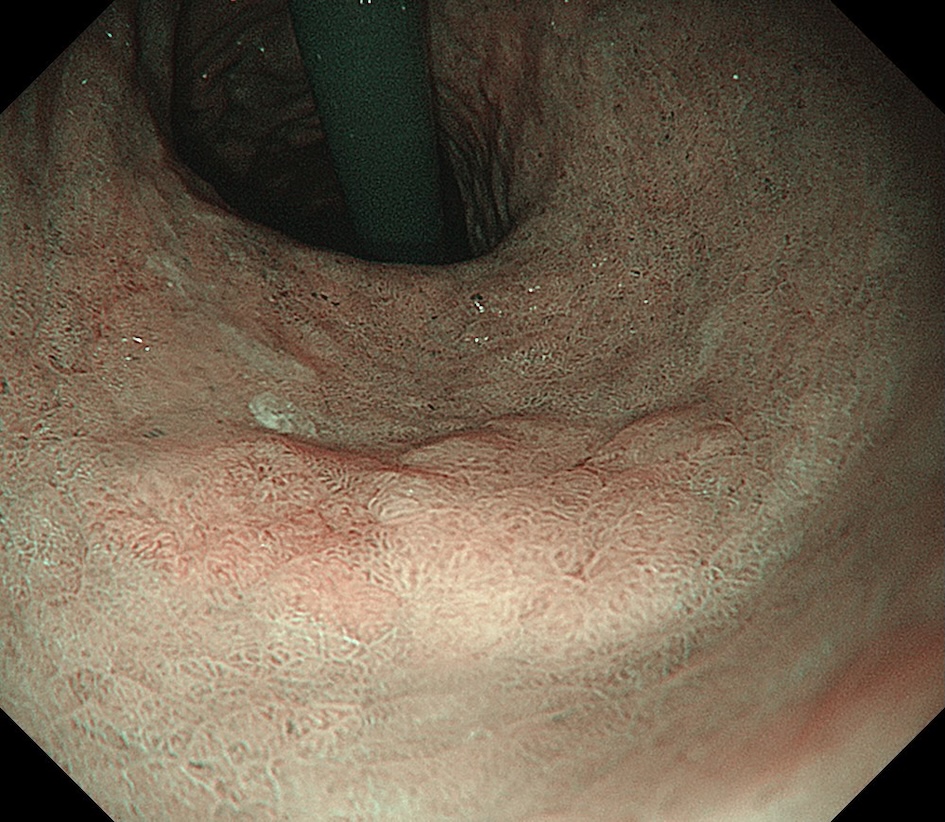

• 白色光観察②(近景)

強調設定:B8

図2

白色光観察:反転し近接観察すると、病変は褪色調を呈する平坦隆起型(0-Ⅱa)病変として認識される。病変左側(前壁側)の一部に淡い発赤を認める。